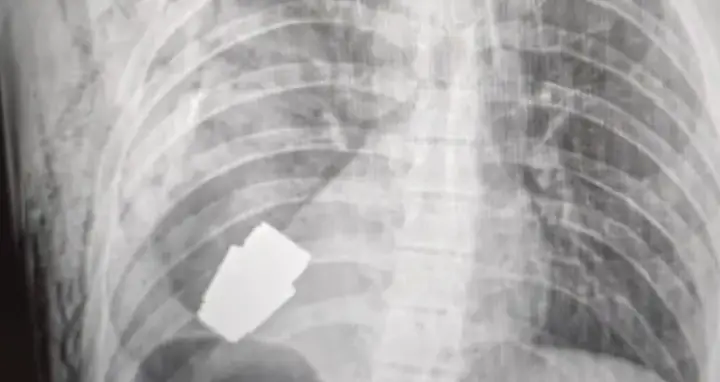

Photos showing an X-ray of the soldier's chest were posted to the Ukrainian armed forces medical service's Facebook page.

A second picture showed a surgeon gingerly holding the device after carefully removing it from the soldier's chest, where it had landed just next to his heart.